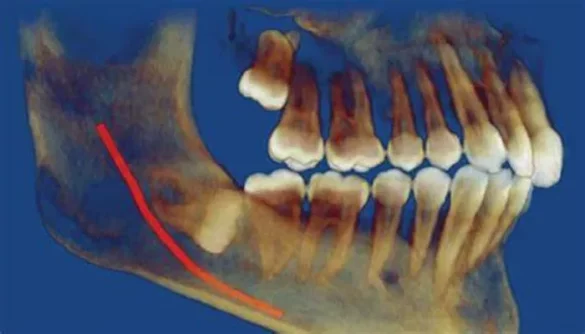

When a wisdom tooth is fully impacted, it means that it remains completely embedded within the jawbone or soft tissue and fails to erupt through the gum line. This occurs due to lack of space or misalignment. Unlike partially impacted teeth, which break through the gum to some degree, fully impacted teeth are invisible without the help of X-rays.

Dentists use advanced imaging to locate the position and orientation of the impacted tooth. Panoramic X-rays and CBCT provide a full view of bone structure, nerve positioning, and any surrounding pathology.

Evaluating Root Development

Removal is easier and safer before the roots are fully developed. Imaging allows dentists to determine the stage of development and predict complications more accurately.